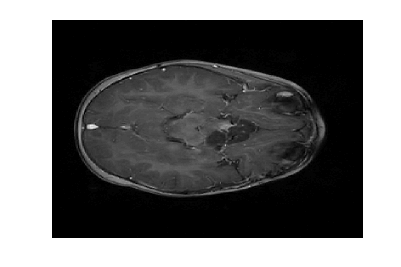

Figure 3 displays the reconstruction MSNR for the various test cases as cataloged in Table 1. Figures 1 and 2 display some examples of reconstructed images for cases of interest.

Due to its wide use in image processing, we consider the use of gradient sparsification with LACS-MRI. We show below that it is possible to produce image reconstructions with significantly higher Reconstruction SNR using gradient sparsification. We have repeated some of the simulations from above for different compression levels, , using the gradient transform to sparsify instead of the wavelet transform. We will refer to this as ”LACS-MRI with gradient sparsity.” We compared the performance of each sparsification method at each compression level using LACS-MRI and then compared this to the L1-W method. Again, we use a reference image and a follow-up image that we hope to recover as in Figure 8. We consider here only the phantom image, as it serves as a prime candidate for gradient sparsification, and is small enough that evaluation of all PDFs is computationally feasible.